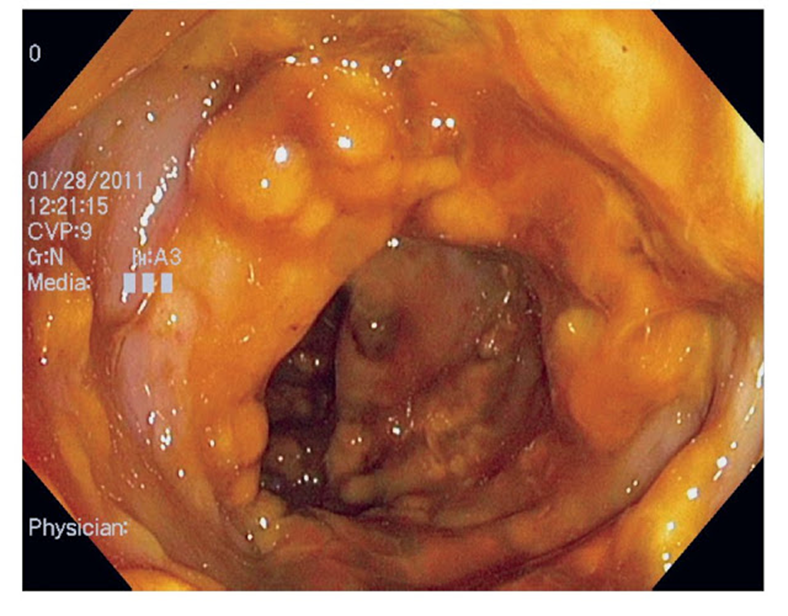

Las mucosas son particularmente vulnerables al ataque de Cándida, tanto las bucales como las vaginales, del mismo modo puede atacar el tracto gastrointestinal como en esta imagen de un esófago severamente afectado. En el sistema interno de órganos ocasionan problemas en los pulmones, visión y corazón que pueden llegar a ser fatales.